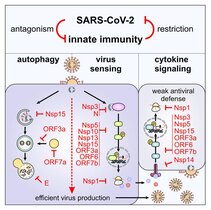

In einer neuen Studie wurden entscheidende Unterschiede in der Signalweiterleitung antiviraler Warnsysteme entschlüsselt. Eine darauf aufbauende…

Forschende der Universität Ulm haben untersucht, wie das neue Coronavirus das menschliche Immunsystem unter seine Kontrolle bringt. In der Studie, die…